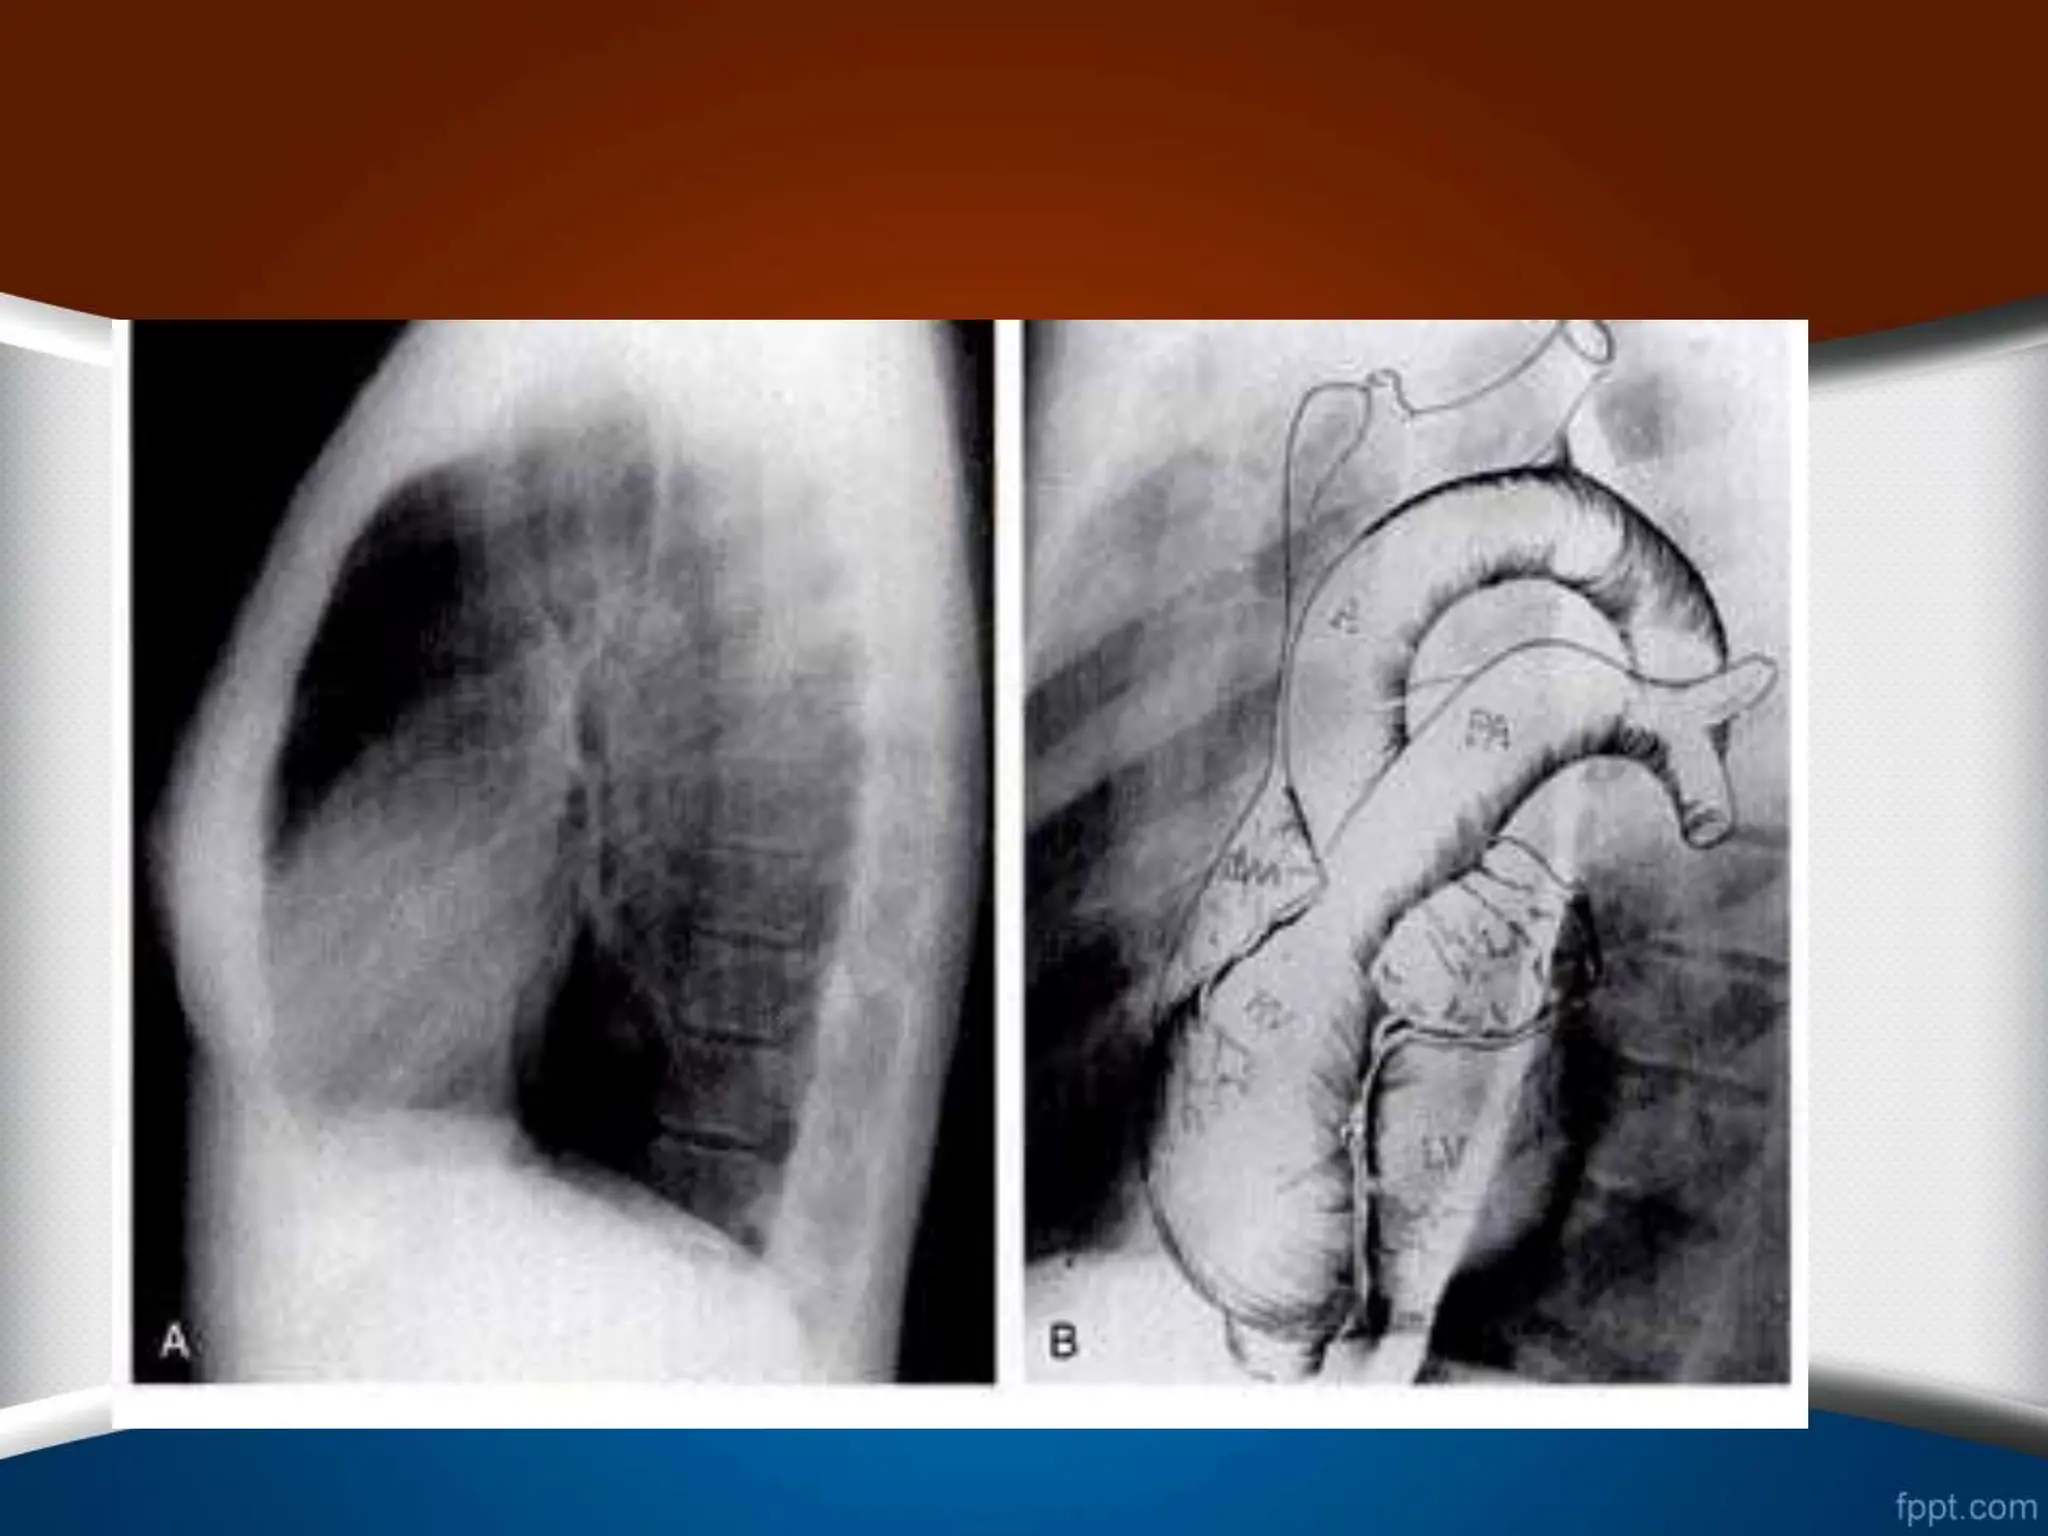

‫است‬ ‫کننده‬ ‫کمک‬ ‫نیز‬ ‫لترال‬ ‫رادیوگرافی‬ ‫از‬ ‫استفاده‬

.

‫در‬

‫بزرگی‬ ‫موارد‬

LV

‫در‬ ‫و‬ ‫رتروکاردیاک‬ ‫فضای‬ ‫شدن‬ ‫پر‬ ،

RV

‫بی‬ ‫به‬ ‫رترواسترنال‬ ‫فضای‬ ‫شدن‬ ‫پر‬ ،

‫ش‬

‫از‬

30

%

‫تا‬

50

‫شود‬ ‫می‬ ‫دیده‬

‫بطن‬ ‫یا‬ ‫و‬‫چپ‬ ‫بطن‬ ‫بزرگی‬ ‫از‬ ‫ناشی‬ ‫کاردیومگالی‬ ‫علت‬ ‫افتراق‬ ‫راست‬ • ‫کننده‬ ‫کمک‬ ‫قلبی‬ ‫بیماری‬ ‫سابقه‬ ‫و‬ ‫حال‬ ‫شرح‬ ‫به‬ ‫توجه‬ ‫است‬ . ‫پولمونر‬ ‫تنه‬ ‫اتساع‬ ‫و‬ ‫ریوی‬ ‫قلبی‬ ‫بیماری‬ ‫مثال‬ ‫برای‬ ‫به‬ ‫شک‬ ‫آئو‬ ‫اتساع‬ ‫طرفی‬ ‫از‬ ‫و‬ ‫افزاید‬ ‫می‬ ‫را‬ ‫راست‬ ‫بطن‬ ‫بزرگی‬ ‫رت‬ ‫م‬ ‫افزایش‬ ‫را‬ ‫چپ‬ ‫بطن‬ ‫بزرگی‬ ‫وجود‬ ‫احتمال‬ ‫نیز‬ ‫صعودی‬ ‫ی‬ ‫دهد‬ • ‫است‬ ‫کننده‬ ‫کمک‬ ‫نیز‬ ‫لترال‬ ‫رادیوگرافی‬ ‫از‬ ‫استفاده‬ . ‫در‬ ‫بزرگی‬ ‫موارد‬ LV ‫در‬ ‫و‬ ‫رتروکاردیاک‬ ‫فضای‬ ‫شدن‬ ‫پر‬ ، ‫بزرگی‬ ‫موارد‬ RV ‫بی‬ ‫به‬ ‫رترواسترنال‬ ‫فضای‬ ‫شدن‬ ‫پر‬ ، ‫ش‬ ‫از‬ 30 % ‫تا‬ 50 % ‫شود‬ ‫می‬ ‫دیده‬ .